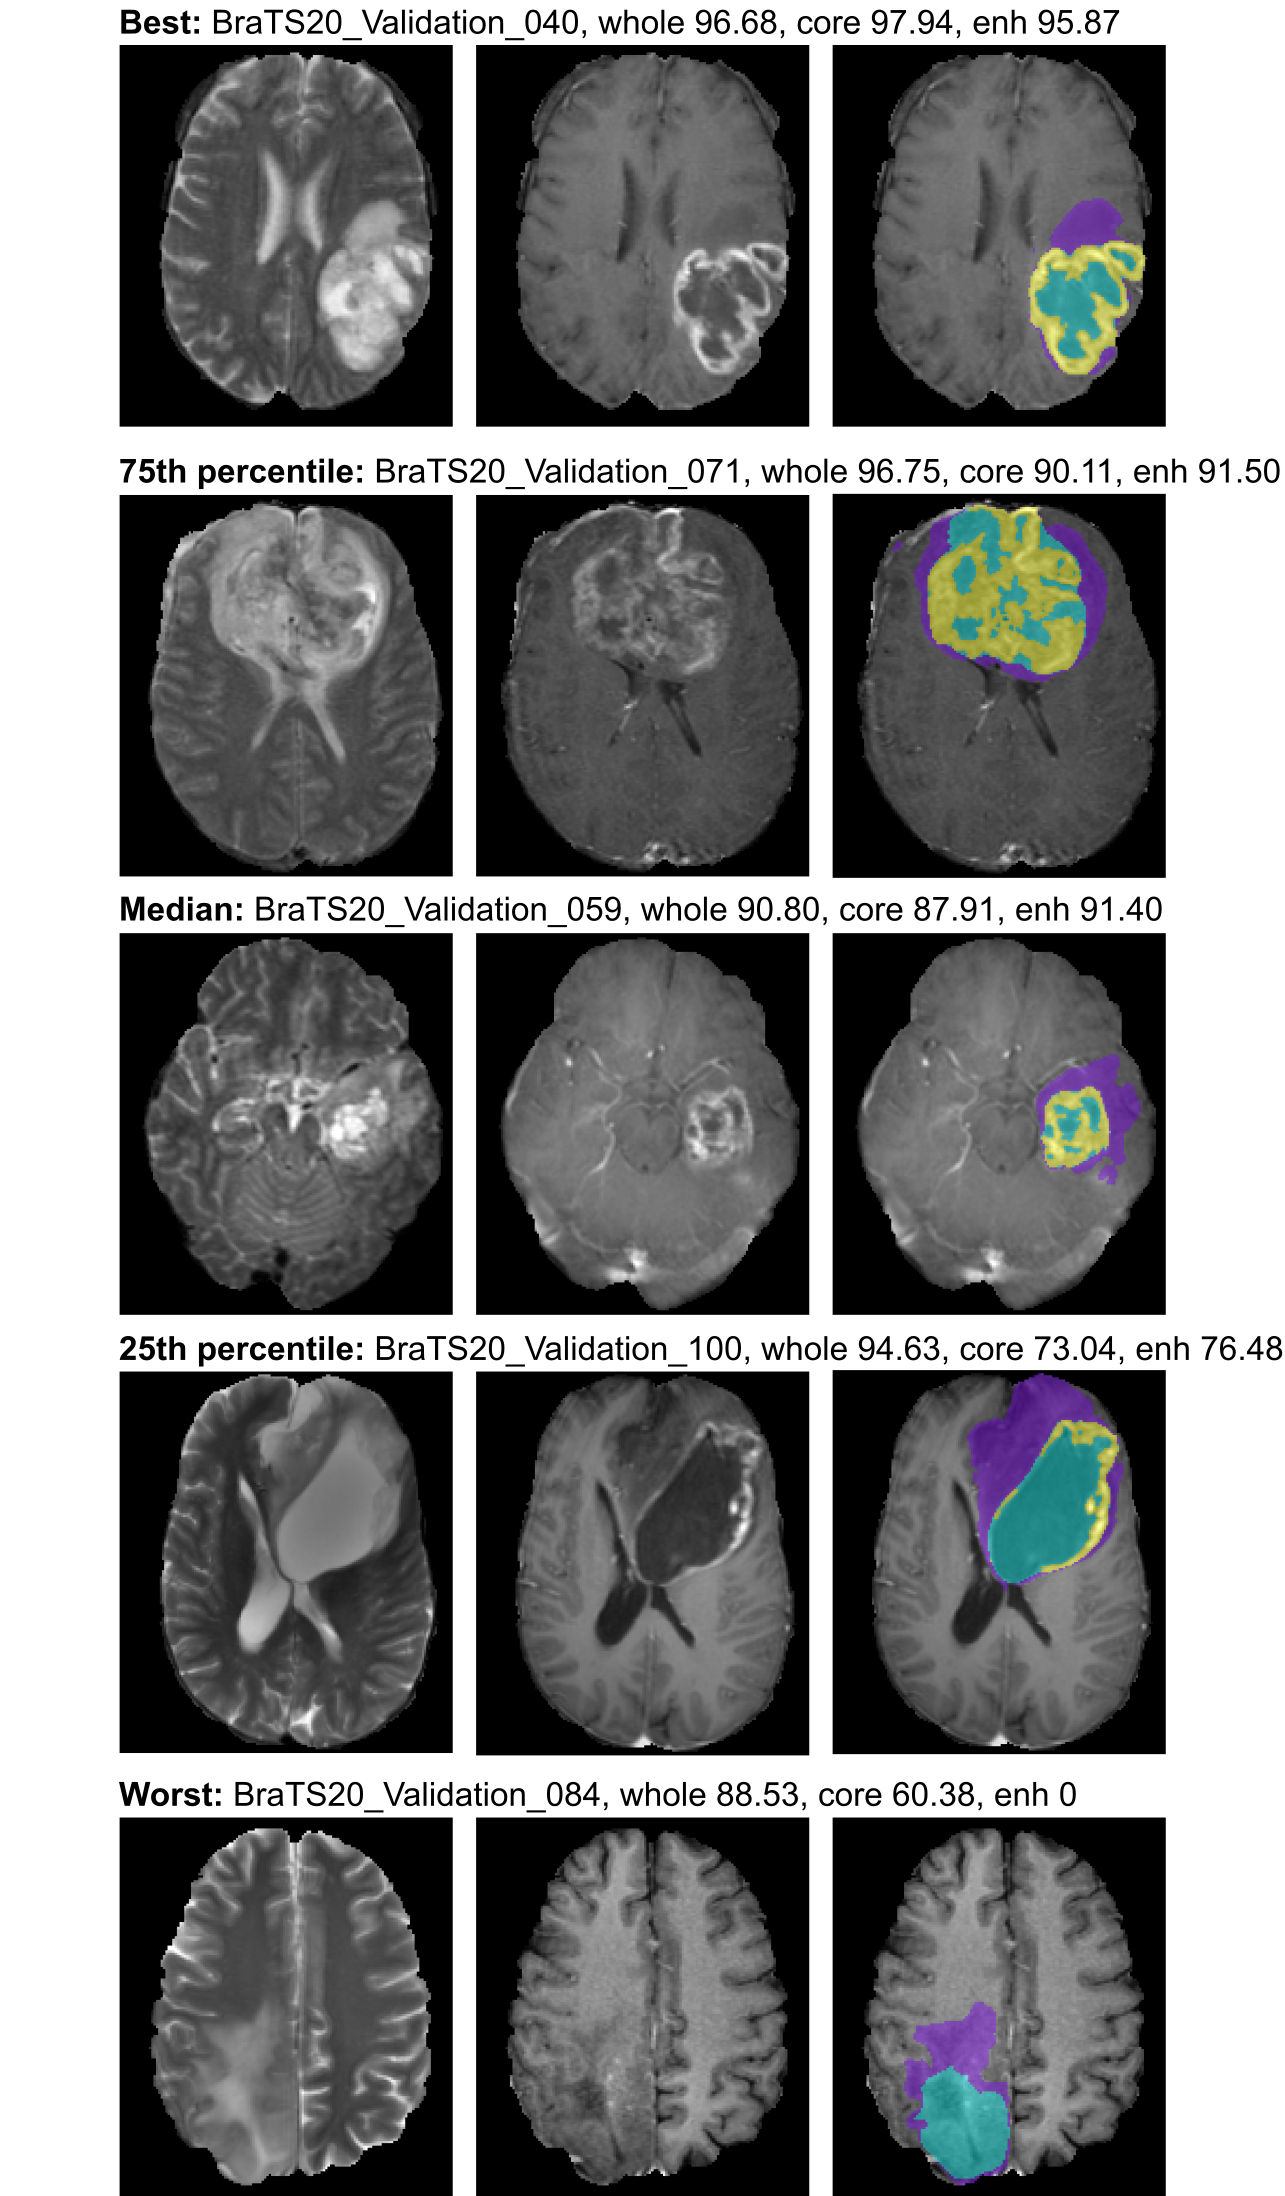

Figure 2: Qualitative validation set results. Cases were selected as best, worst, median and 75th and 25th percentile. Within each row, the raw T2 image is shown to the left, the T1c image in the middle and on overlay with the generated segmentation on the T1c image is shown on the right. Edema is shown in violet, enhancing tumor in yellow and necrosis/non-enhancing tumor on turquoise.

Figure 2 provides a qualitative overview of the segmentation performance. It shows results generated by our ensemble on the validation set. To rule out cherry picking we standardized the selection of presented validation cases: They were selected as best, worst, median and 75th and 25th percentiles based on their Dice scores (averaged over the three validation regions). As can be seen in the figure, the segmentation quality is high overall. The low tumor core score for the worst example hints at one of the potential issues with the definition of this class in the reference segmentations (see Discussion). The enhancing tumor score of 0 in the absence of predicted enhancing tumor voxels indicates either that our model missed a small enhancing tumor lesion or that it was removed as a result of our postprocessing. An inspection of the non-postprocessed segmentation mask reveals that the enhancing tumor lesion was indeed segmented by the model and must have been removed during postprocessing.

Based on our observations in Figure 2, one major source of error appears to be the tumor core prediction. In particular the worst presented example has a rather low Dice score for this region, even though the result seems visually plausible. We believe that this failure mode is not necessarily an issue inherent to our model but potentially originates from an inconsistency in the definition of the non-enhancing tumor and necrosis label, particularly in LGG cases. While the necrosis part of this label is easy to recognize, the non-enhancing tumor region often has little evidence in the image and the associated annotations may be subjective.